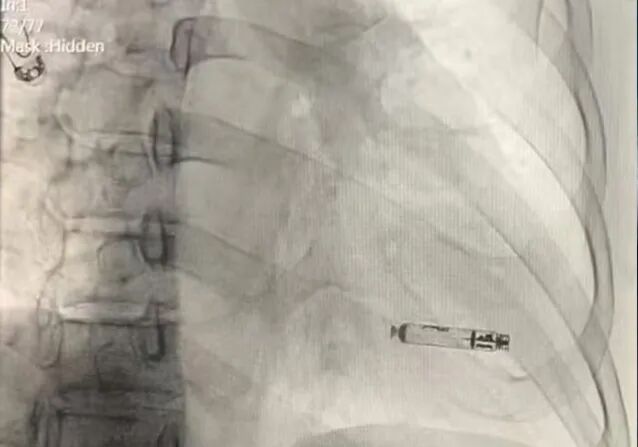

术后右前影像

术后左前影像